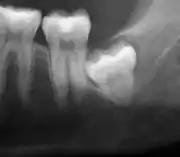

If the tooth cannot be assessed with clinical exam alone, the diagnosis is made using either a panoramic radiograph or cone-beam CT. Where unerupted wisdom teeth still have eruption potential several predictors are used to determine the chance of the teeth becoming impacted. The ratio of space between the tooth crown length and the amount of space available, the angle of the teeth compared to the other teeth are the two most commonly used predictors, with the space ratio being the most accurate. Despite the capacity for movement into early adulthood, the likelihood that the tooth will become impacted can be predicted when the ratio of space available to the length of the crown of the tooth is under 1.[5]: 141